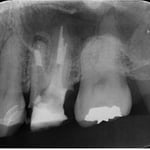

患者さんは何度説明しても虫歯の治療,虫歯の治療と思っていますが,これは根管治療です。上顎第一大臼歯の3本の主たる根管(神経や血管の入っていた管)を神経を取った後に感染を起こし,再治療の際,3本中の2本の管から大量の膿が排出してきた瞬間です。

神経を除去した後でも,その後の処置がしっかりしていないと,管の中に細菌が繁殖し,骨の中に炎症を起こした結果,このように膿が溜り,激痛が生じます。

爪は硬い組織です。ゆえに,詰めの内部で内出血を起こしても,腫れるに腫れられません。ですので,爪に注射針などで穴をあけ,内圧を開放してあげることによって,痛みから解放されます。私自身,体験もしており,痛みが強すぎて,深夜に親指の周囲に麻酔をしたことがあります。歯の根の中の細菌感染によって生じる痛みもまったく同様の理由です。

当然ながら,中古のホースでどこかに劣化があれば,そこから水は漏れます。新品ならば,漏れることろがなくて,ホースは,壊れるまでパンパンに膨らむでしょう。この動画はホースの蛇口を開放してあげた状態です。これで,痛みは徐々におさまります。対処療法としては抗生物質を投与することもありますが,レーザーを当ててもよくはなりません。